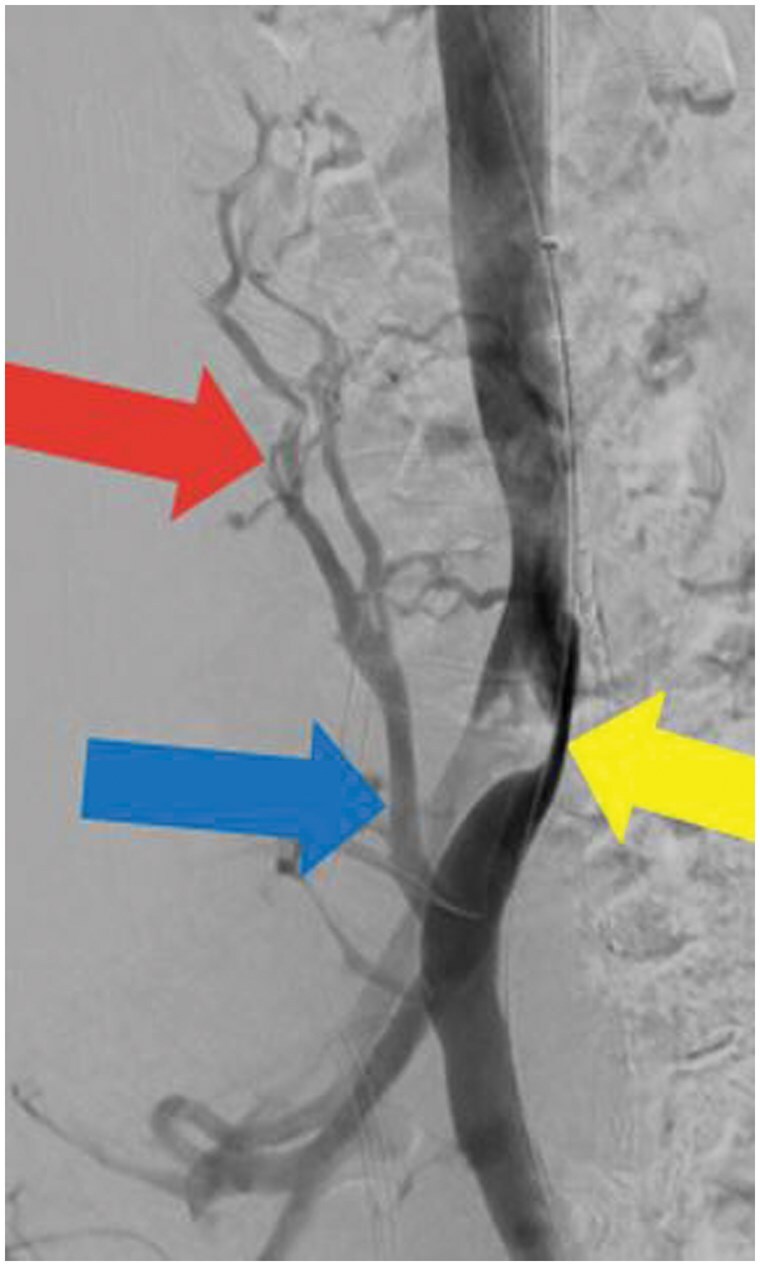

May-Thurner生理(MTP)可导致各种充血综合征,由于右髂总动脉(RCIA)压迫左髂总静脉(LCIV)。这种压迫可能导致通过腰静脉的静脉回流,导致脊髓硬膜外静脉丛(EVP)充血,这可能导致顽固性头痛。本病例报告详细介绍了一例伴有MTP的严重难治性新发持续性头痛患者的临床过程,该患者接受了腰升静脉(ALV)栓塞术。患者为59岁女性,每日持续性头痛3年,多次偏头痛预防治疗和微创手术均无效。影像学研究显示RCIA对LCIV有明显压迫,ALV血流逆行,EVP充血。患者接受了ALV栓塞治疗,症状明显缓解。在22个月的随访中,头痛严重程度降低了80%,患者不再需要常规的头痛药物。此外,通过性腺静脉栓塞治疗相关盆腔充血综合征解决了长期相关的盆腔疼痛和压力。本病例强调了静脉充血在难治性头痛综合征中的作用,并强调了靶向静脉干预的潜力,如栓塞,在其管理中。研究结果扩展了将静脉压迫综合征与头痛病理生理联系起来的新证据,并支持探索干预策略作为选定患者的可行治疗选择。需要进一步的研究来验证这些发现,并为临床实践建立循证指南。

May-Thurner physiology (MTP) can lead to various congestion syndromes due to compression of the left common iliac vein (LCIV) by the right common iliac artery (RCIA). This compression may result in venous reflux through the lumbar vein, leading to congestion of the spinal epidural venous plexus (EVP), which could contribute to refractory headaches. This case report details the clinical course of a patient with severe refractory new daily persistent headache associated with MTP who underwent ascending lumbar vein (ALV) embolization. The patient is a 59-year-old female with a 3-year history of daily persistent headache which failed multiple migraine prevention therapies and minimally invasive procedures. Imaging studies revealed significant LCIV compression by the RCIA, retrograde ALV flow, and EVP congestion. The patient underwent ALV embolization, resulting in significant symptomatic relief. At the 22-month follow-up, headache severity reduced by 80%, with the patient no longer requiring routine headache medications. Additionally, treatment of associated pelvic congestion syndrome through gonadal vein embolization resolved longstanding associated pelvic pain and pressure. This case highlights the role of venous congestion in refractory headache syndromes and underscores the potential of targeted venous interventions, such as embolization, in their management. The findings expand on emerging evidence linking venous compression syndromes to headache pathophysiology and support exploring interventional strategies as viable treatment options for selected patients. Further research is needed to validate these findings and establish evidence-based guidelines for clinical practice.